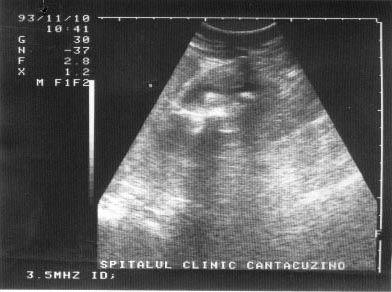

Figura 16. Intarire acustica posterioara la nivelul vezicii urinare.

Figura 17.}ntarire acustica posterioara la nivelul V.B.